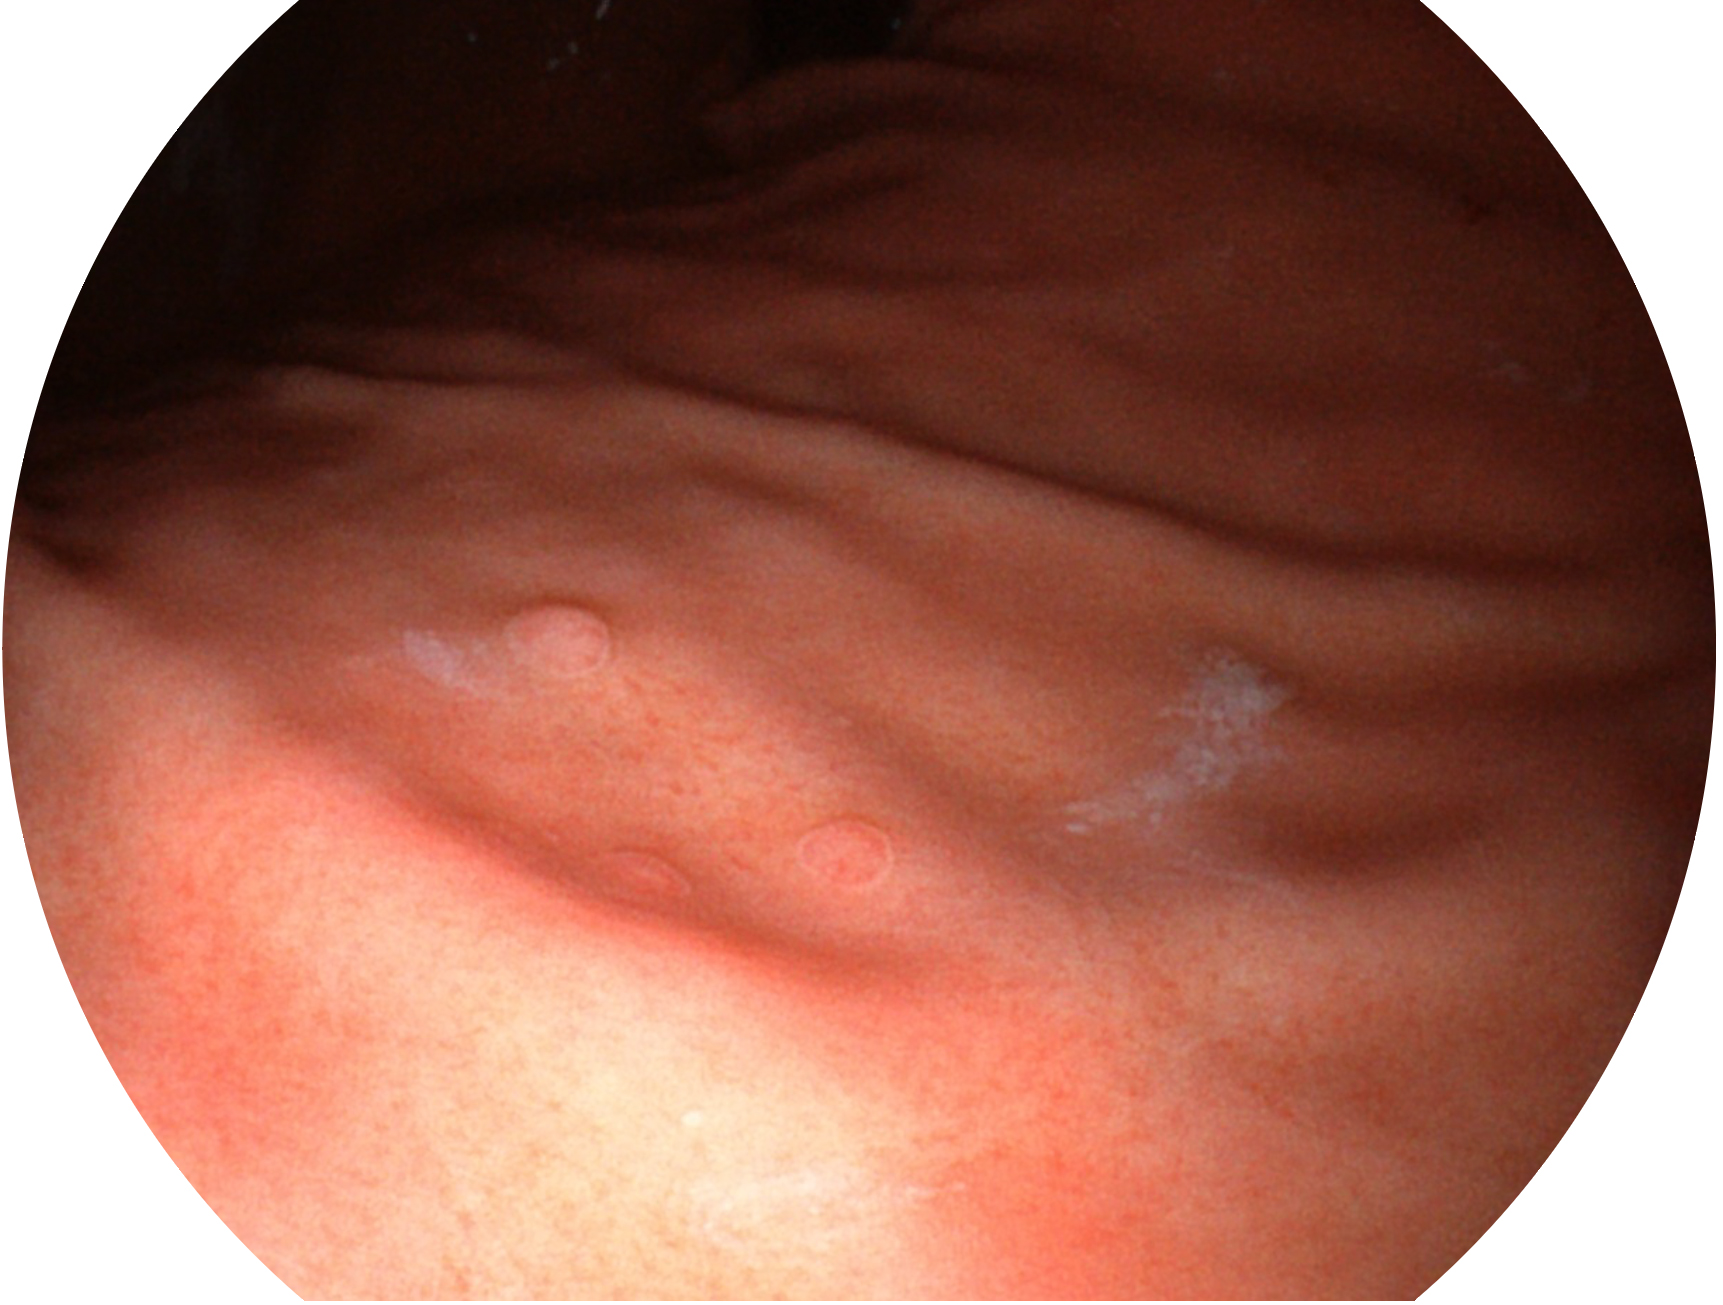

• 白光图像 VIST图像